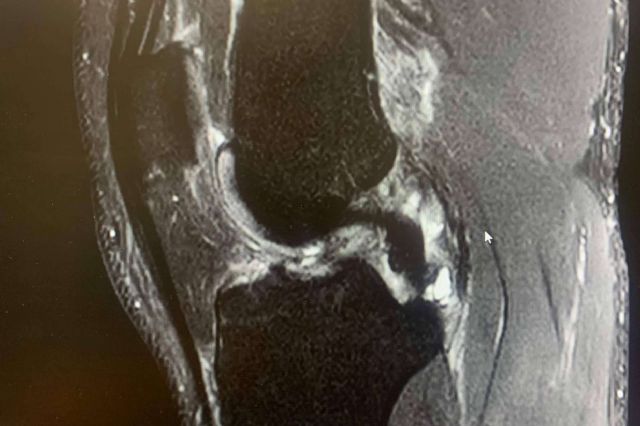

El ligamento cruzado anterior es una banda de tejido fuerte y resistente que se encuentra en la rodilla y juega un papel crucial tanto en la estabilidad como en la capacidad de control de esta articulación.

Las lesiones de LCA suelen ocurrir en situaciones en las que la rodilla está sometida a un estrés repentino y excesivo, sobre todo cuando la pierna está en apoyo y se somete a una torcedura en valgo (“metiendo la rodilla hacia dentro”) o con una torsión de la pierna hacia afuera con torsión interna del muslo, con la rodilla en flexión.

Inestabilidad articular: La sensación de que la rodilla se "mueve" o "falla" al apoyar puede ser un síntoma característico de una lesión del LCA. Se puede sentir que la rodilla no es tan estable como antes y que se desplaza incontrolablemente.

Derrame articular: Si el traumatólogo lo tiene que extraer mediante punción para aliviar la presión y el líquido es rojo (“hemático”), es probable que se trate de una lesión del LCA, aunque puede tener otras causas.